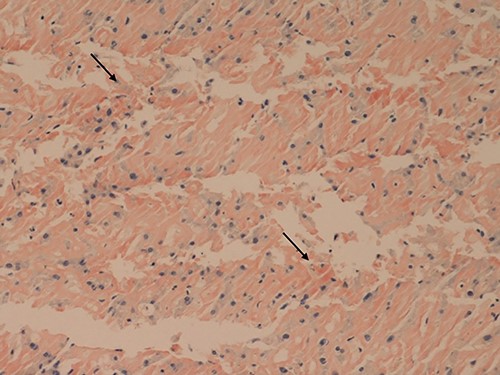

Her liver biochemistry continued to deteriorate so a transjugular liver biopsy was performed. Histology from both liver and duodenal biopsies was consistent with amyloidosis on Congo red staining (Figs 1 and 2, respectively). A subsequent bone marrow biopsy, organized by the haematologists, revealed a low level infiltrate of plasma cells consistent with multiple myeloma.

Liver core biopsies (Congo red, x20): the amorphous material in the sinusoids demonstrates salmon pink staining under standard light microscopy in keeping with amyloid deposition.